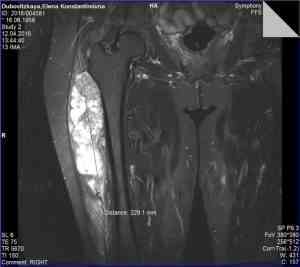

• МРТ/КТ мягкотканевых опухолей (рис. 3 и 4);

Рисунок 3. МРТ-картина саркомы мягких тканей правого бедра